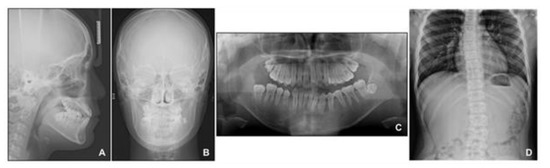

When the patient reached 13 years of age, he claimed that his teeth were still not fitting well. He showed a mild chin point deviation toward the right side, and severe lip canting while smiling was still present. The lateral facial profile was maintained favorably after the phase 1 treatment, but the Becker’s nevus area on the right cheek through the upper neck was more prominent, with hypertrichosis (Figure 7 and Figure 8). Intraorally, all permanent teeth except the second molars had successfully erupted; however, the hypertrophic region in the anterior mandible was still present. Therefore, he showed severe canting of mandibular anterior teeth with a 1 mm deviation of the apical base midline of the mandibular dentition toward the right side.

At this point, we noticed that the nevus, facial asymmetry, lip canting, and hypertrophy of alveolar bone occurred in the same area. Taking into consideration these symptoms, we suggested the presence of “Becker’s nevus syndrome” for the simultaneous occurrence of Becker’s nevus and other systemic anomalies. We interviewed the patient, and he informed us that he had been recently diagnosed with scoliosis by an orthopedist (Figure 8D). Fortunately, the severity of the scoliosis was incipient to moderate, with no need for active treatment but only a need for observation.

Figure 8. Radiographs before phase 2 treatment: (A) Lateral cephalogram; (B) Posteroanterior cephalogram; (C) Panoramic radiograph; (D) Standing anteroposterior radiograph of spine showing scoliosis.